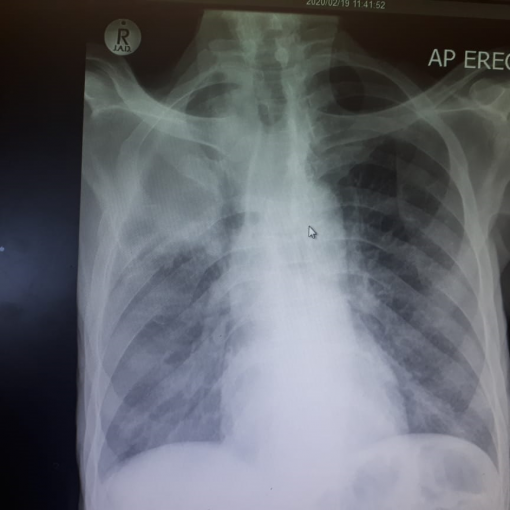

A classic case of Cushing Disease

HOSP # 165965617 WARD Endocrine Ward CONSULTANT   Dr Heleen Vreede DOB/AGE 33 y female Abnormal Result Salivary Cortisol = 36 nmol/L Presenting Complaint Struggling with a right hand abscess –